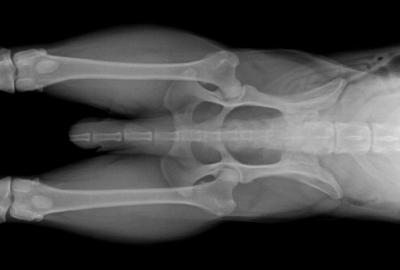

RTG Dysplazie loketního kloubu (DLK)